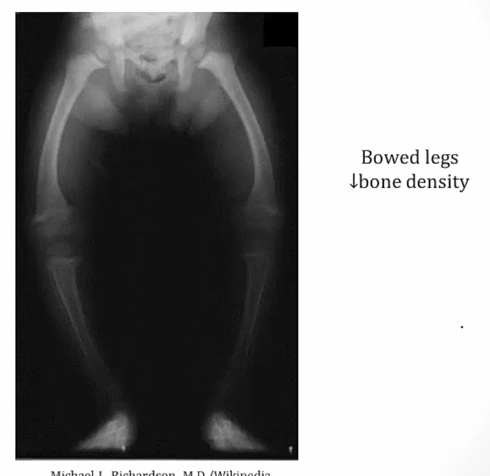

Rickets

Osteomalacia